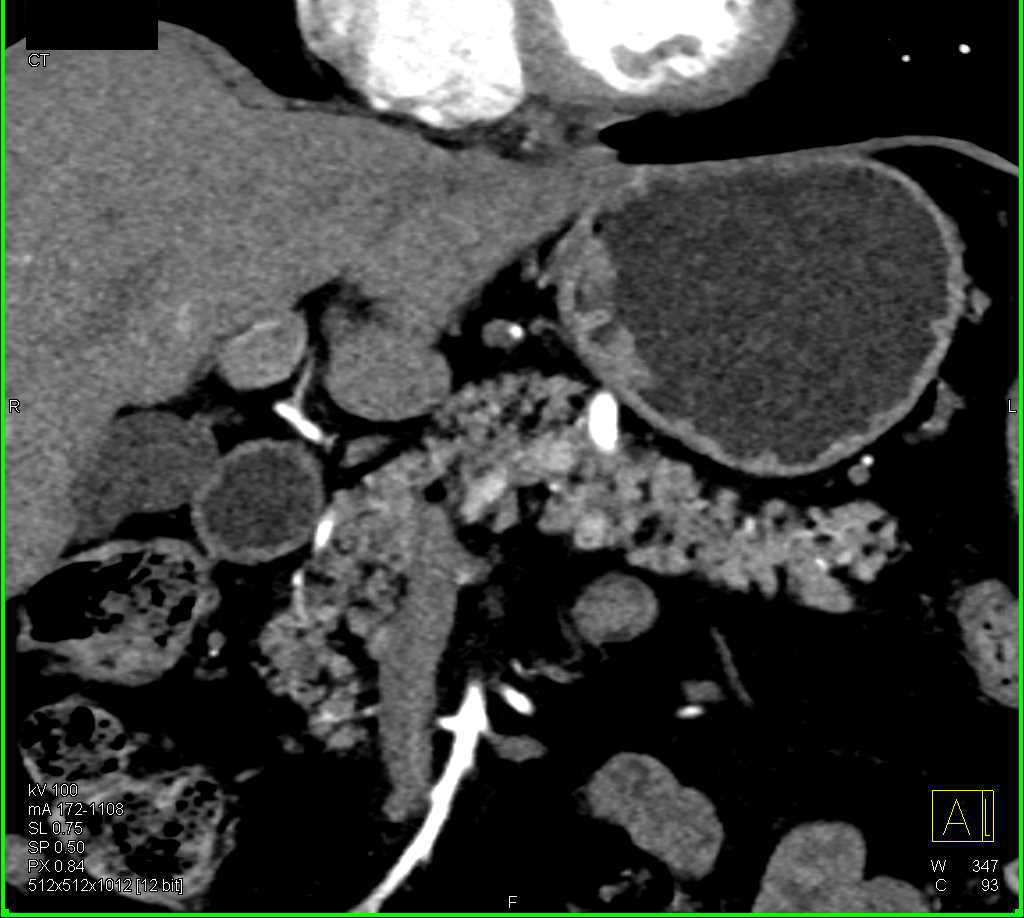

Recurrent Renal Cell Carcinoma to Contralateral Kidney and the Pancreas